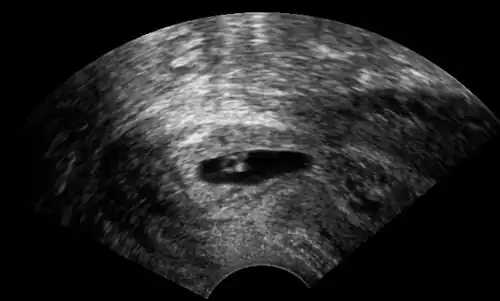

Ultrasonography of a cervical pregnancy. doi: 10.15347/WJM/2014.011